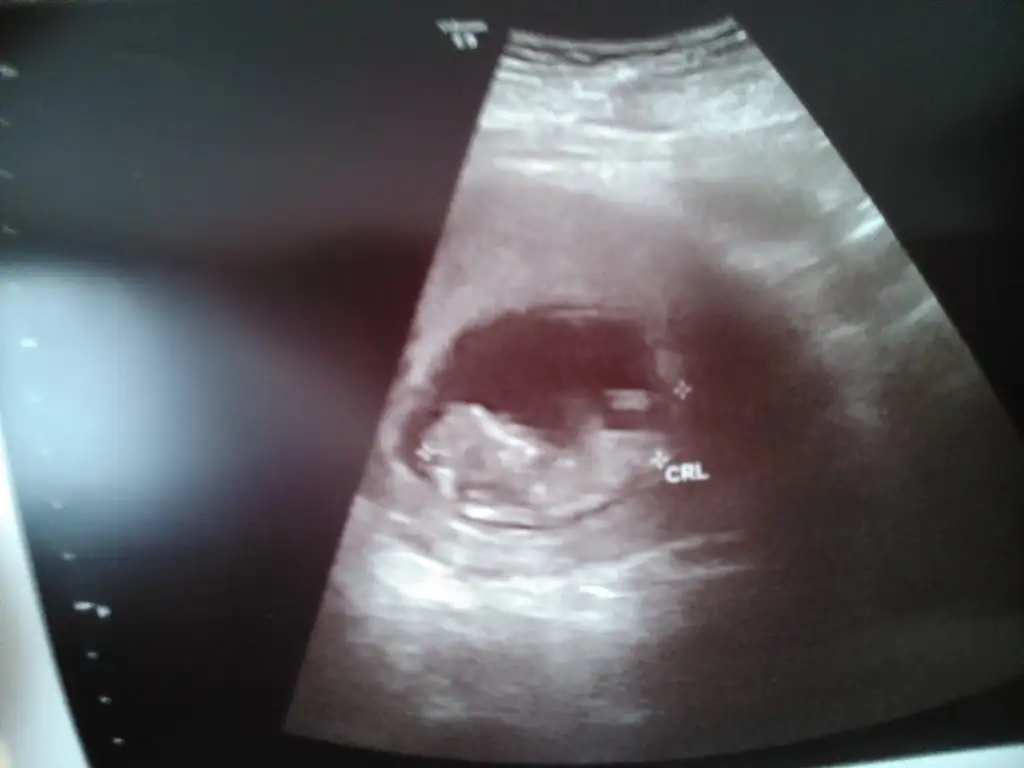

Evet Haklısın konunun BAŞINDA öle yazıyormuş surrender bu durumda erkek olması gerekli bakalım tutacakmı ? Allah hayırlısını nasip etsin herkes sağsalim alsın bebeişlerini kucağına sevgiler...

Yorumun icin cok tesekkurler, bende erkek hissediyorum, ama nub teorisi konusunda 2 arkadas kiz gibi dedi, bakalim saglikli olsunda, ama iki kizim var oglum olsun isterim tabi